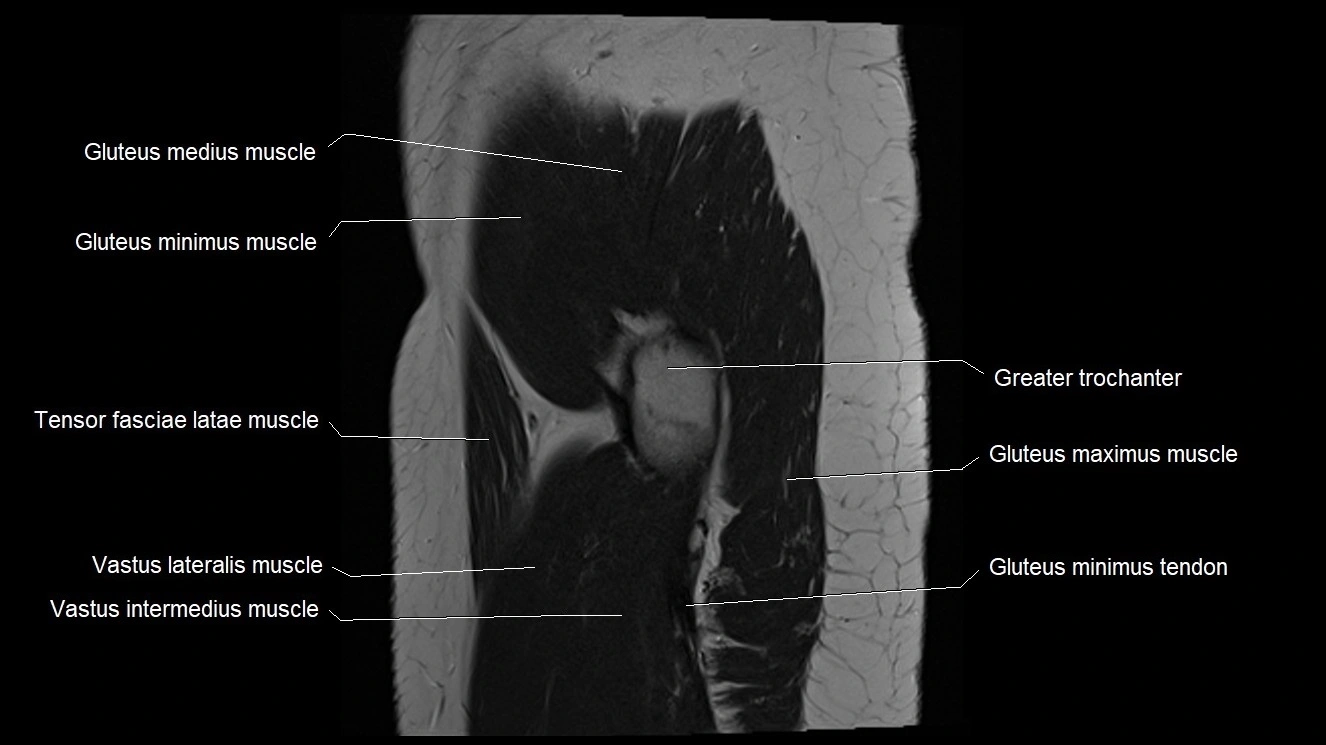

- Gluteus medius muscle

- Gluteus minimus muscle

- Gluteus minimus tendon

- Greater trochanter

- Gluteus maximus muscle

- Tensor fasciae latae muscle

- Vastus intermedius muscle

- Vastus lateralis muscle